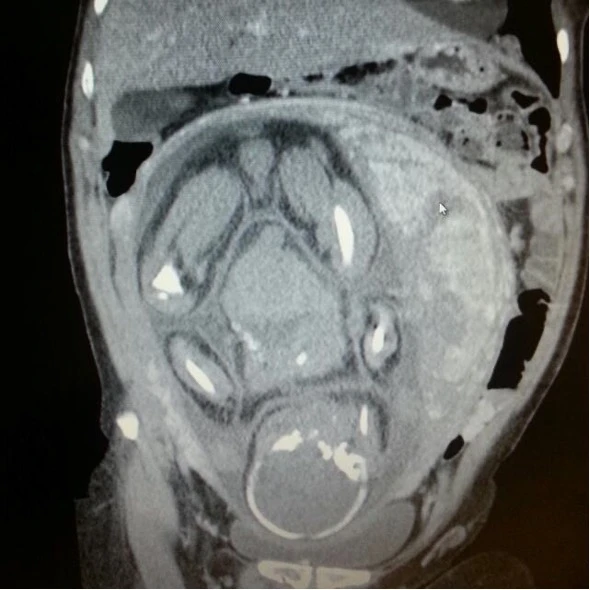

CT-scanner thoraco-abdominal d’une patiente à 34 semaines d’aménorrhées se présentant avec une clinique de douleur thoracique et un syndrome de la veine cave supérieure. Il est rare de voir de telles images. En effet, les radiographies standards et les CT-scanners, injectés ou non, exposent tant la mère que le fœtus aux risques liés aux irradiations. Ces examens doivent donc faire l’objet de consilium avant d’être effectués chez une femme enceinte. Des techniques d’imagerie qui n’exposent pas aux irradiations, comme l’ultrason ou l’IRM, sont considérées comme sûres durant la grossesse. La littérature n’a mis en évidence aucun effet secondaire de l’IRM durant la grossesse, également durant le premier trimestre.

Le diagnostic posé chez cette patiente était finalement une volumineuse masse médiastinale avec compression vasculaire et thrombose de la veine cave supérieure se propageant jusqu’à la veine cave inférieure.